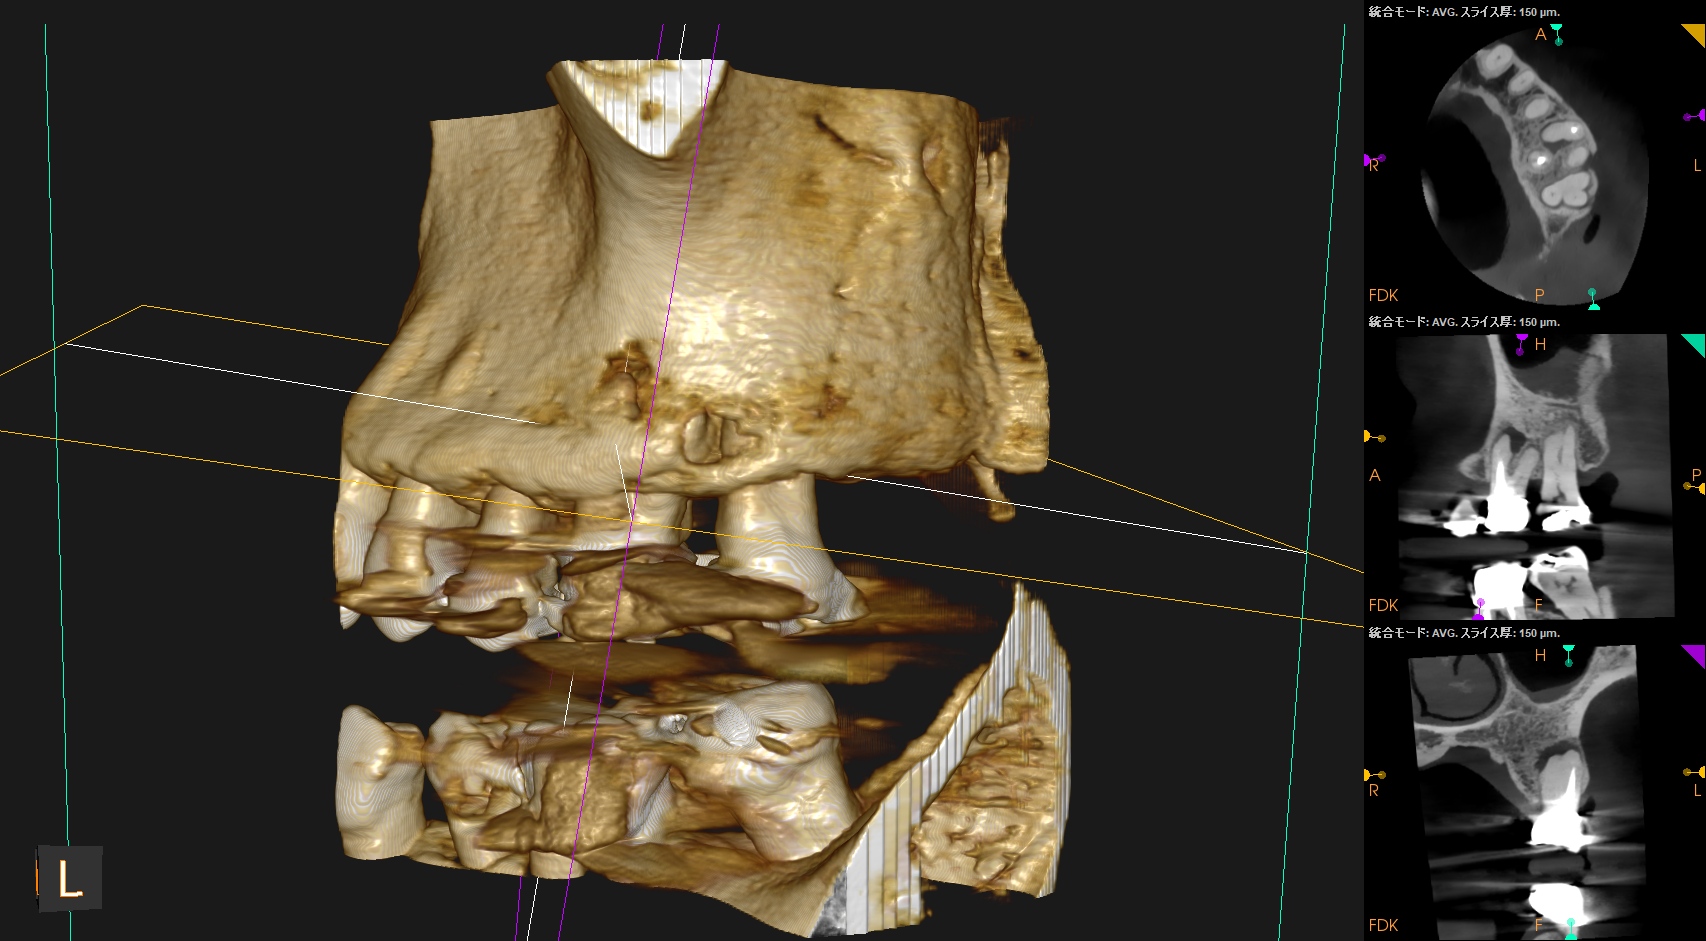

口蓋根を再根管治療していた歯牙のApicoectomyだ。

MB,DBは外科時には以下のようになる。

DBは楽だが、MBは頬舌径が7.4mmでMB1, MB2があるという…難ケースだ。

逆根充後にPA, CBCTを撮影した。

MB

DB

P

B